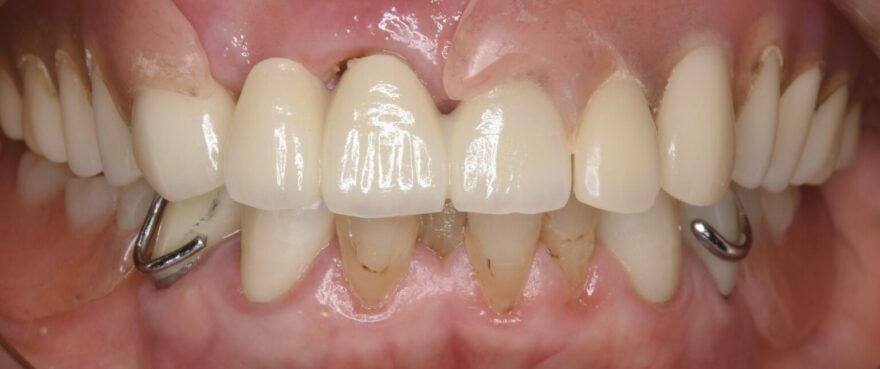

術前の口腔内写真

上下ともに、両側に入れ歯を使用されていました。入れ歯のバネにより、残っている歯もぐらついてきています。

入れ歯を付けた状態です。

一見歯があるようには見えますが、金属のバネが見えてしまい、歯茎との境目も気になります。

また、硬いものは噛めないので食べられるものも限られ、健康にも良くありません。